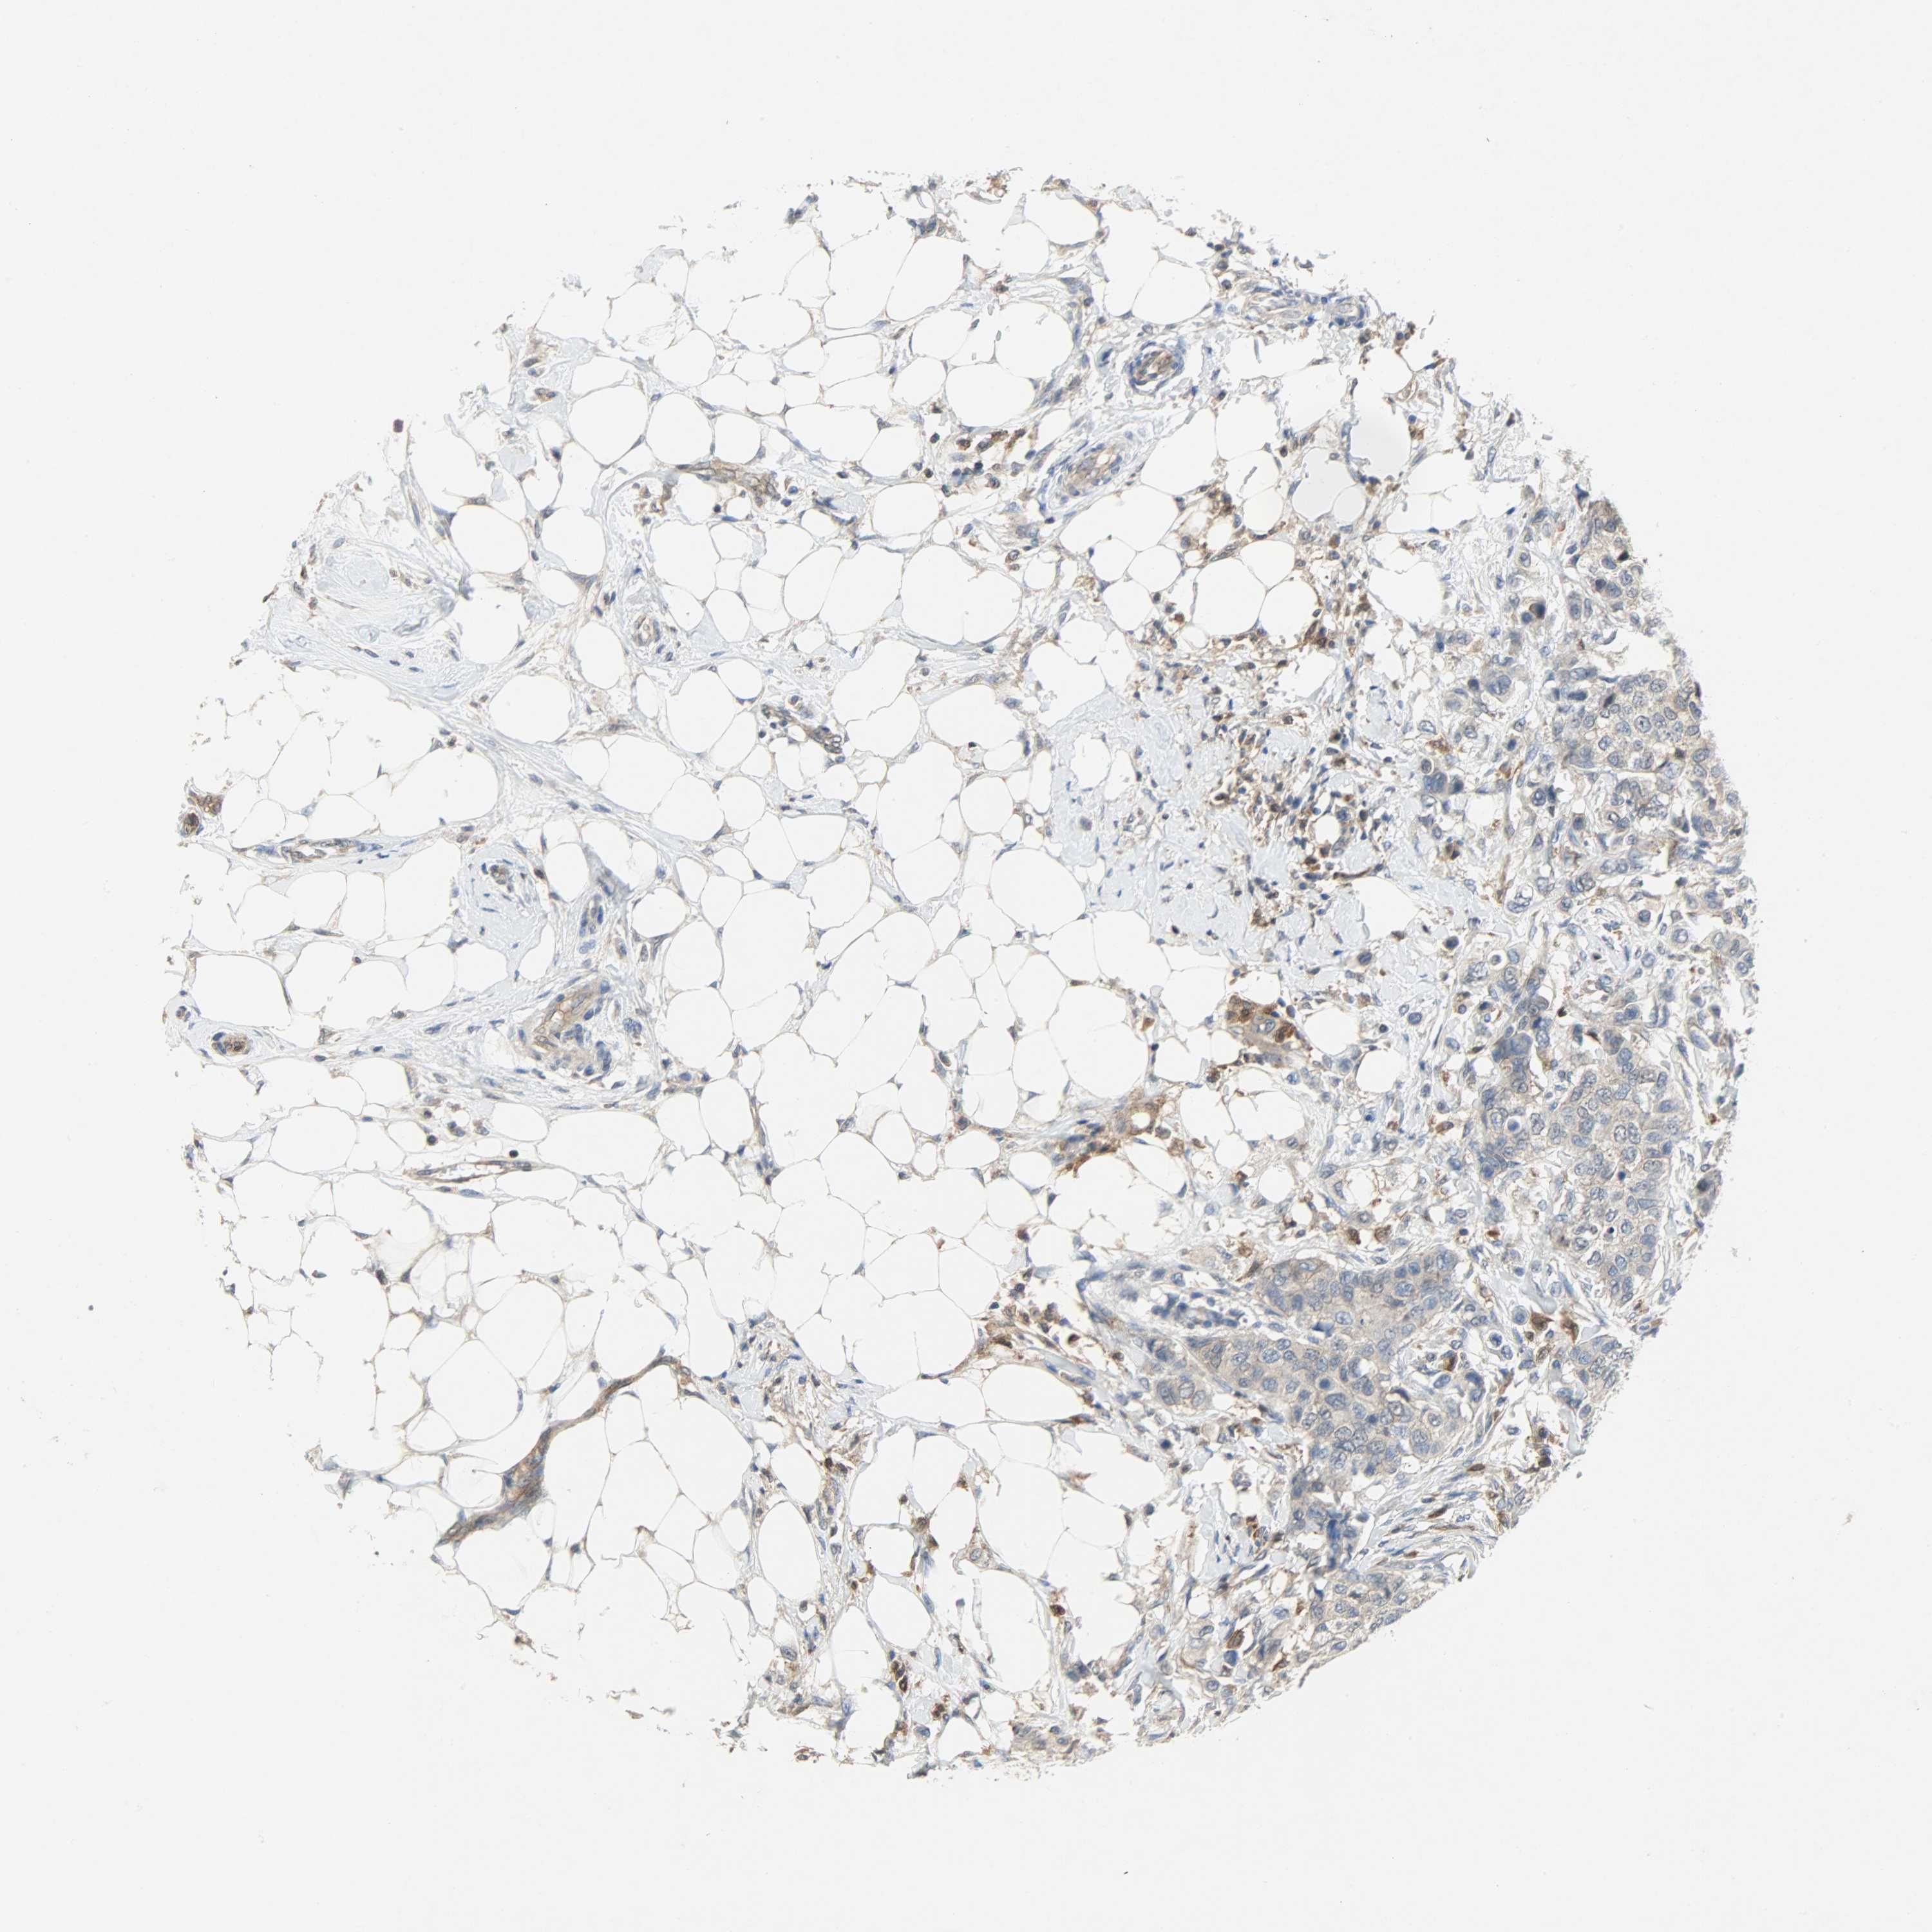

BRCA TCGA BRCA VALIDATION PROTEIN EXPRESSION

ANTIBODIES

AND

VALIDATION